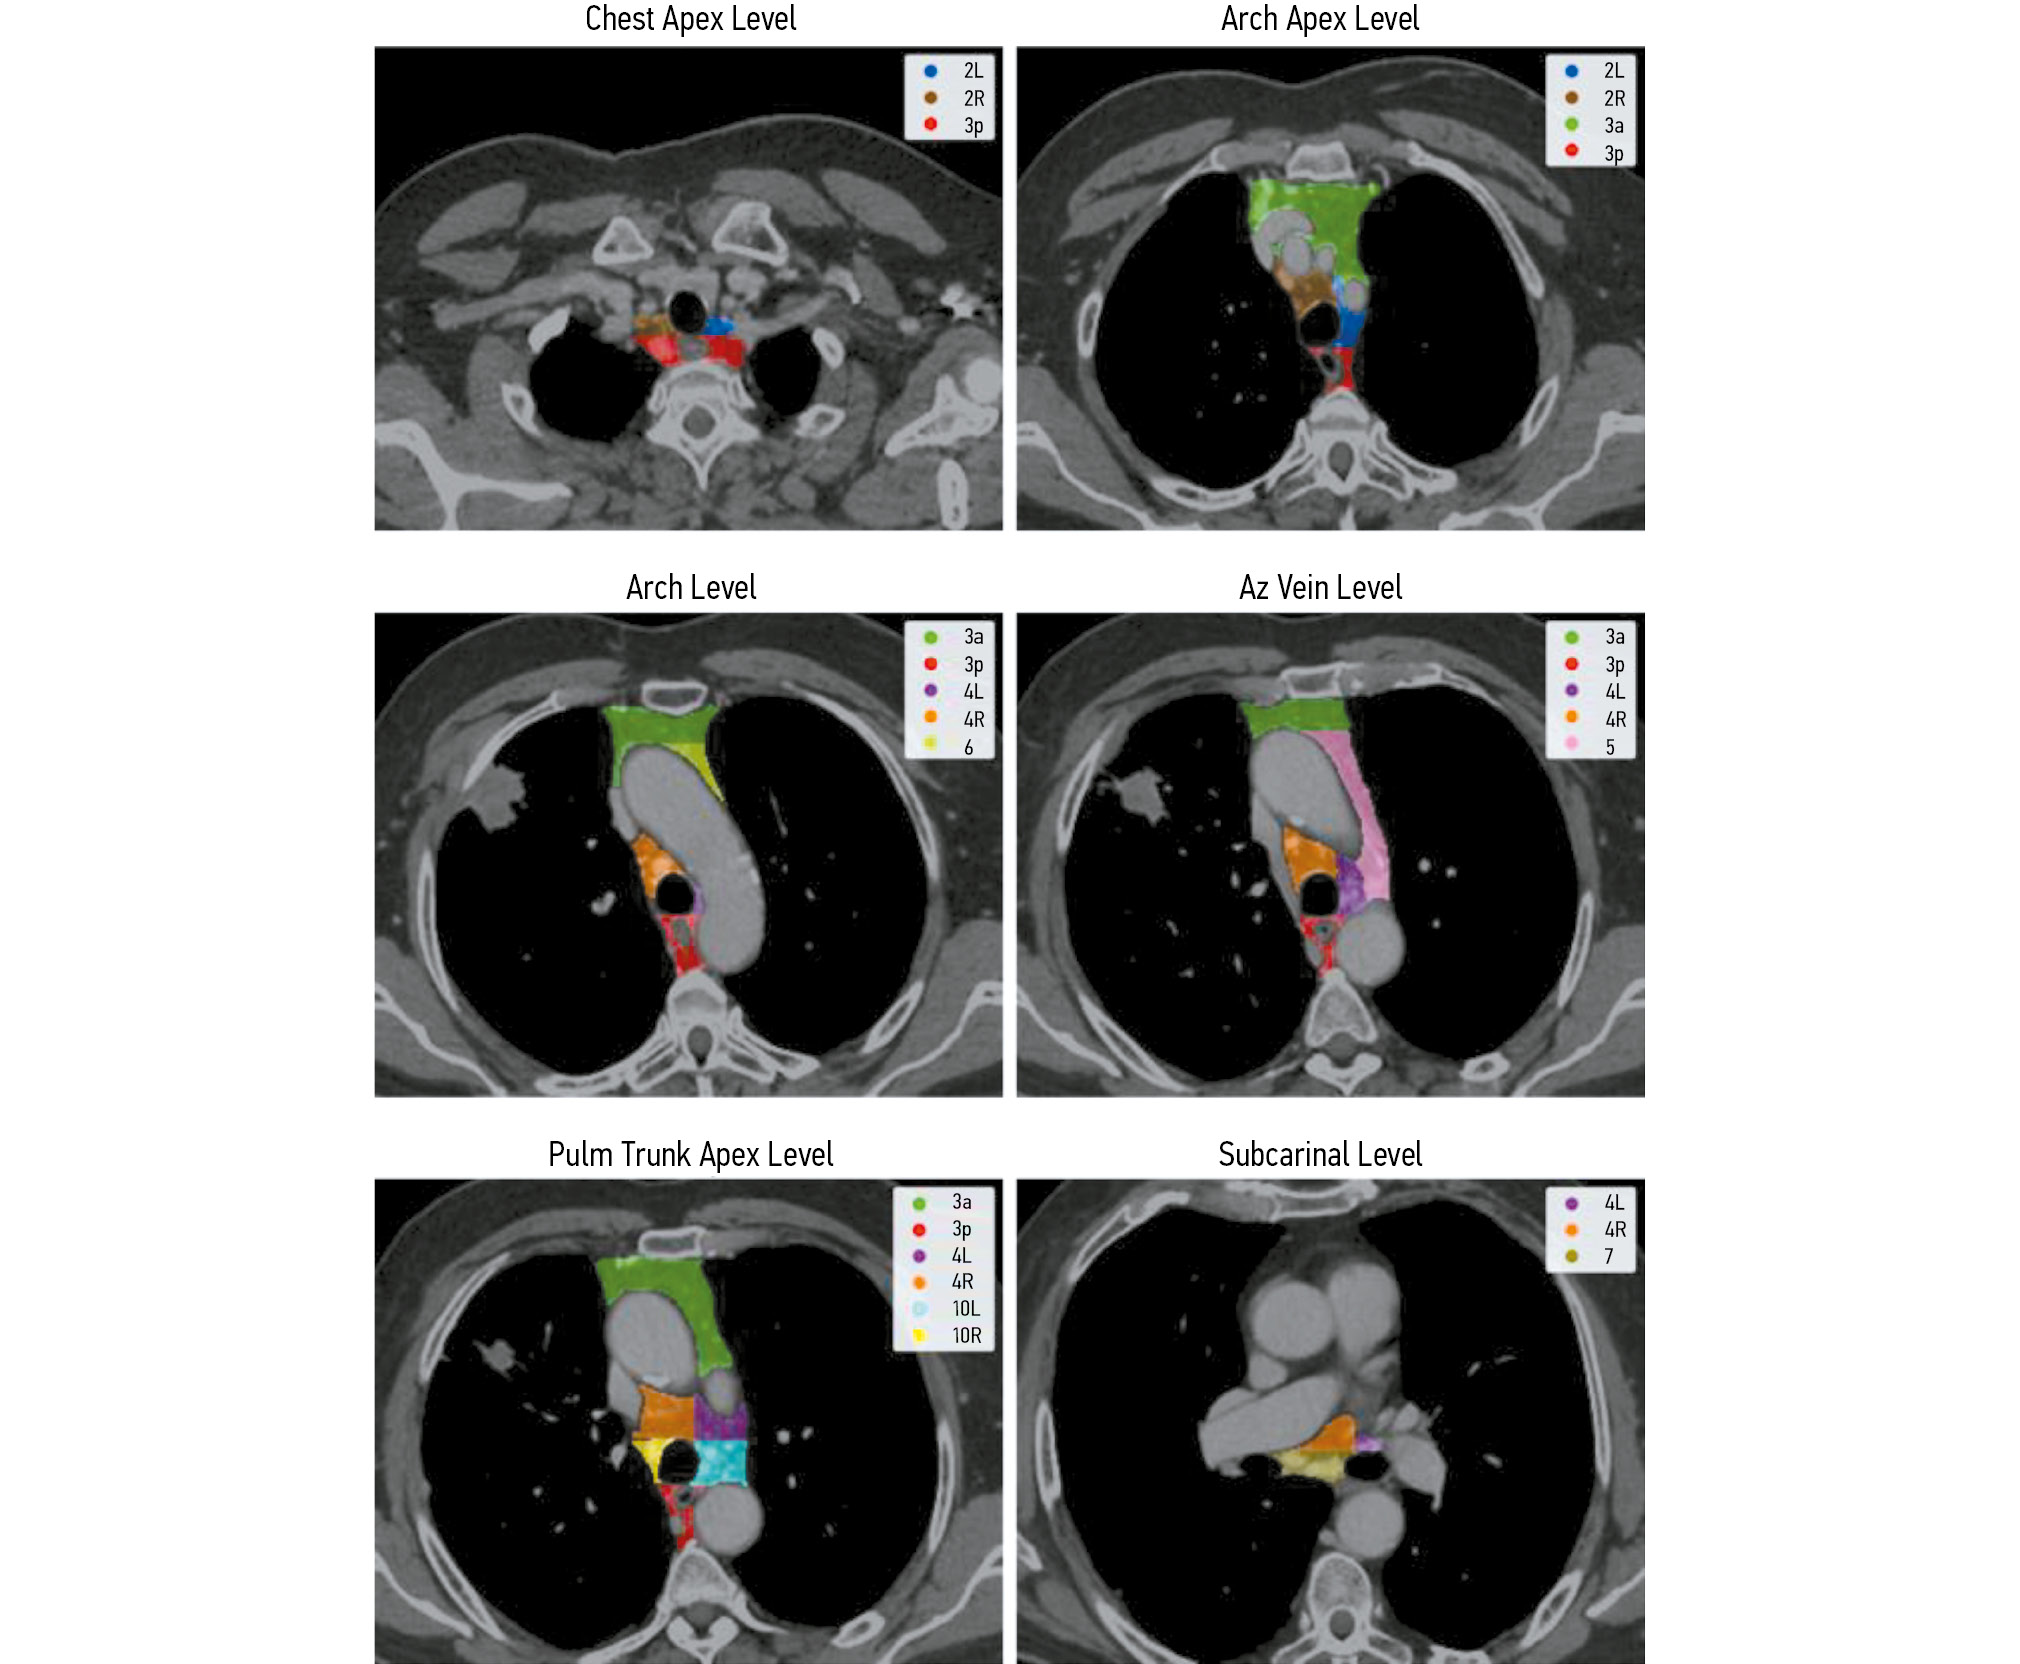

Segmentation of the lymph node groups

In patients with NSCLC, the affected lymph nodes are located in a narrow range (mediastinal area). The anatomical and primary tumor sites dictate the extent of regional lymph node involvement [12]. The International Association for the Study of Lung Cancer (IASLC) guidelines recognize ten lymph node groups in the mediastinum [40]. Lymph node groups near the trachea and bronchi are divided into left and right groups. No additional specialized classification system is used for the subcarinal lymph nodes. During diagnostic procedures, biopsies are not typically performed for Groups 1, 8, and 9 lymph nodes. Therefore, they were excluded from this study.

The same radiologist annotated the lymph node groups, meticulously adhering to the IASLC guidelines for generating prognostic maps for the mediastinum [40]. The annotation protocol required that large blood vessels, such as the aorta, pulmonary trunk, and azygos vein, as well as the esophagus, be differentiated from the lymph node groups (Fig. 2).

Fig. 2. Example of lymph node group annotation at different mediastinal levels.